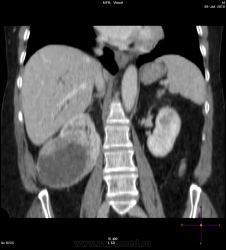

Солитарное кистовидное образование правой почки с неравномерно утолщенными стенками, у узлами в капсуле, накапливающими контраст. Фасция Гарота справа тяжистая. По классификации - киста 4-й категории, крайне велика возможность малигнезации. Может, показалось вовлечение парааортальных лимфоузлов?

В 1986 г. M.A. Bosniak создал “рабочую” классификацию кистовидных образований почек, которая позволяет предположить доброкачественность или злокачественность кистозных образований при распределении их по радиологическим критериям на 4 основные категории. Образования I и II категорий являются заведомо доброкачественными и поэтому нуждаются в динамическом наблюдении или, по показаниям, в лечебной пункции со склеротерапией под контролем УЗИ или КТ. Образования III категории могут быть как доброкачественными, так и злокачественными, а образования IV категории – кистозные почечноклеточные раки.

Третья категория – более сложные кистовидные образования, которые демонстрируют какие-либо радиологические признаки злокачественности. Некоторые из этих образований оказываются доброкачественными (например, сложные кисты, мультилокулярная кистозная нефрома, геморрагические кисты), другие злокачественными (почечные кистозно-клеточные карциномы). Одним из критериев, которые заставляютотнести кистовидное образование почки к III категории, является повышение плотности ее стенки. При КТ у кистовидного образования выявляется плотная (вплоть до обызвествления) стенка по всему периметру кисты, хотя образование может сохранять некоторые признаки простой кисты почки. Следующим критерием является характер отложения кальцинатов. Если при КТ в образовании определяется большое количество кальцинатов, расположенных глыбками (как на периферии образования, так и в центре), если из-за этого стенки и перегородки становятся утолщенными, неправильной формы, то данное образование следует отнести к III категории. Наличие множественных перегородок толщиной более 1 мм, видимых утолщений в месте прикрепления перегородок к стенкам кисты позволяет также отнести данное образование к третьей категории. Большое количество тонких перегородок в образовании определяет его как сложную кисту. Такие образования крайне сложно дифференцировать как доброкачественные или злокачественные, но они чаще по КТ-картине выглядят как злокачественные. При КТ определяется негомогенное многокамерное образование округлой или неправильной округлой формы, возможно с капсулой. Плотность образования неоднородная, пониженная относительно паренхимы, в полости образования видно большое количество перегородок.

IV категория – поражения явно злокачественные, обычно кистозные почечно-клеточные карциномы. Основными симптомами кистозной опухоли при КТ являются: неправильная форма кисты, негомогенность структуры образования с участками некроза, деформация почки, нечеткая граница между кистой и паренхимой почки, плотностные показатели могут быть выше, чем в кистах (+20…+40 Н), т.е. близкие к плотности почечной паренхимы. Капсула имеет неравномерную толщину, часто обызвествлена по периферии. Возможна визуализация дополнительных фокусов образования (кажущееся увеличение образования в размерах и изменение его конфигурации) после введения контрастного вещества. Но самым важным симптомом является увеличение плотности внутреннего содержимого после внутривенного введения контрастного вещества. Часто на серии срезов удается выявить эндофитные гребневидные фестончатые разрастания, выступающие в просвет кистозной полости. Особенно хорошо этот мягкотканый васкуляризированный компонент опухоли проявляется при внутривенном контрастировании

Всё верно, я тоже пользуюсь данной классификацией по Босняку, кистозно-солидное образование правой почки я отнёс к 4 категории, нужно отметить, что преобладает кистозный компонент, но солидный компонент довольно приличный и значительно накапливает контрастное вещество до 80-90HU, четко капсулу образования не отграничить. Ко всему этому в паренхиматозную фазу четко дифференцируются единичные парааортальные и паракавалльные л/узлы. С большей степенью вероятности в данном случае cr почки. Пациентка на следующей неделе будет госпитализирована для верификации.

Описание изменений, выявленных при микроскопическом исследовании: опухоль представлена крупными альвеолярными структурами из светлых, оптически пустых клеток с мелкими гиперхромными ядрами, опухоль частично инфильтрирует капсулу почки, полностью прорастает стенку почечной лоханки, образуя полиповидные структуры. Одиночные опухолевые эмболы в сосудах почки. Отдельно присланный узел представлен тканью почки с опухолевым узлом, строение которого соответствует выше описанной опухоли. В воротах почки патологических образований не найдено. Во всех исследованных лимфоузлах (6 шт.) метастазы опухоли с замещением всей ткани лимфоузлов.

Патоморфологическое заключение: массивный светлоклеточный почечно-клеточный рак почки с частичной инфильтрацией капсулы, прорастанием в ЧЛС, опухолевыми эмболами в сосудах, множественными метастазами в забрюшинные лимфоузлы (6 шт